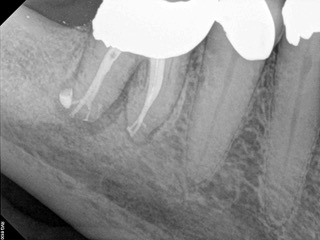

A body of research has emerged in recent years on the management of severe dental pain, exemplified by the diagnosis of an acute apical abscess where drainage cannot be achieved, symptomatic apical periodontitis, or irreversible pulpitis.11 An example of an acute apical abscess is depicted in Figure 1 and Figure 2. These conditions typically represent the most severe discomfort experienced by patients, and consequently, they serve as an excellent model for pain management. Treatment strategies for these issues and other painful conditions should include both definitive treatments for the diagnosed condition as well as adjunctive pharmacologic management.

(1.) A 74-year-old male presented with an acute apical abscess associated with tooth No. 30. The pre-operative periapical x-ray revealed evidence of apical pathology.

Figure 1

(2.) The infection was managed with oral antibiotics, root canal therapy, and a combination of ibuprofen and acetaminophen to manage the preoperative and postoperative discomfort.

Figure 2